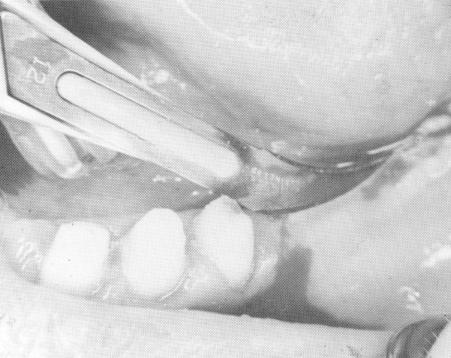

Fig. 11-3. Incising the tissue. (From Linkow, L. I.: The blade vent, a new dimension in endosseous implantology, Dent. Concepts 11:3-18, 1968.)

1 Incising the tissue before dental bladevent insertion